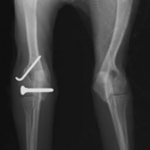

症例3:キルシュナーワイヤーのピンニングによる整復

ペルシャ猫 11ヶ月齢 雄

他院にて左大腿骨遠位の成長板骨折(salter-harrisⅠ型)が認められており、治療相談を目的として来院。当院にて、キルシュナーワイヤーを用いたピンニングにより骨折部位の整復を行いました。術後の経過は良好で、現在も経過観察中です。

術前レントゲン

術後レントゲン